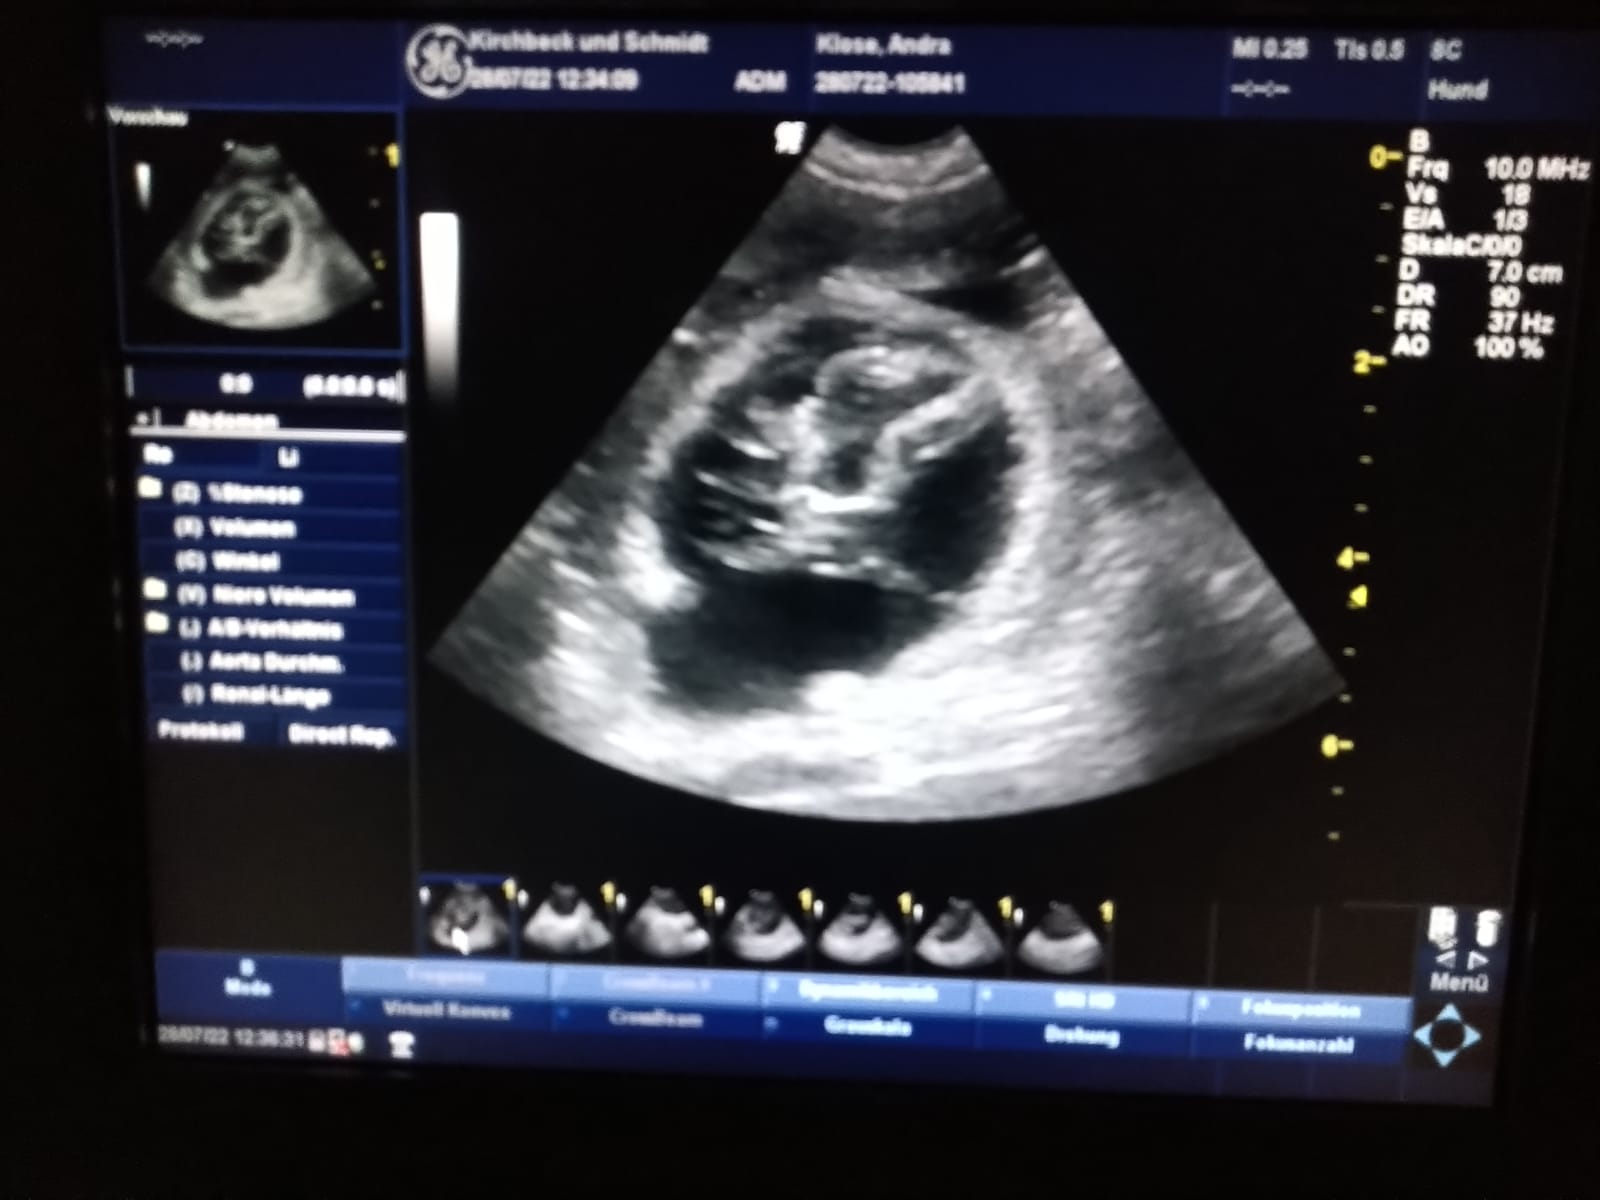

Gestern waren wir bei unseren Tierärztinnen Kirchbeck und Schmidt in Dülmen. Unsere erste Ultraschalluntersuchung.

Wir waren mal wieder begeistert wie ruhig, entspannt und liebevoll die Untersuchung durchgeführt worden ist. Auf das Rasieren unter dem Bauch haben wir verzichtet und die Untersuchung wurde im Stehen durchgeführt. Sofort haben wir die gefüllten Fruchblasen auf dem Monitor sehen können, ein tolles Erlebnis. Wir freuen uns nun unbeschreiblich auf die nächsten 33 Tage.